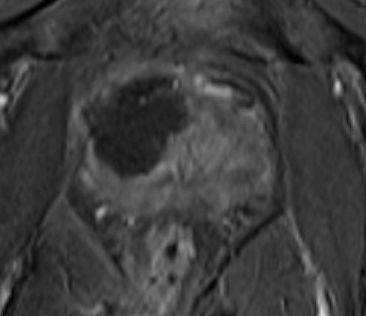

I've put 3 MRI images taken in November 2015. Compare these with my earlier ones below that, from 24 November 2014. Whilst not commenting specifically on these, the consultant said that the overall MRI had not revealed any significant (observable) prostate cancer.

The image below shows the cryo ablated (destroyed) area-

the

dark area. The

surgeon says "it looks very good", so I presume that means he ablated an ideal area.

(Remember: "left" in the image is the right hand side of my body)

I must say, the area ablated looks

much larger than the red area marked on my

first MRI. However, the surgeon did say that he would target an area a little larger than that, to be sure all the index lesion was killed off, plus I guess the precision of the cryo comes into play.